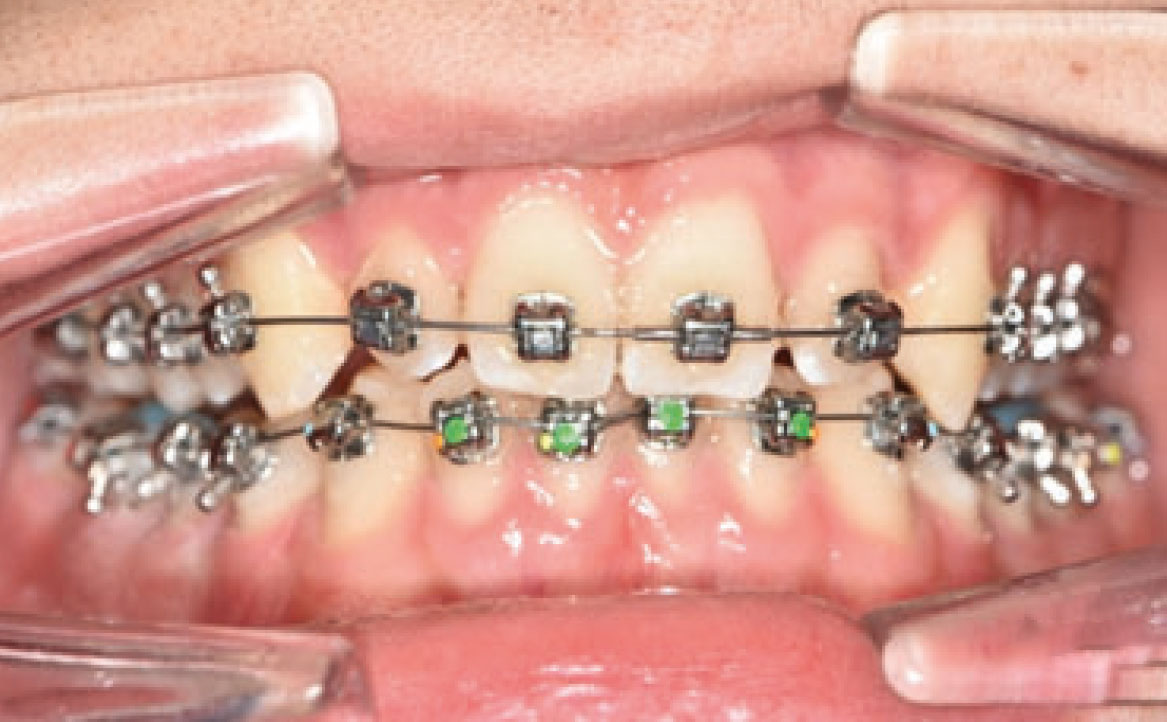

Un mese dopo, durante il secondo controllo, è stata raggiunta la posizione dei molari richiesta e, di conseguenza, il Carriere Motion è stato sospeso e si è iniziato il trattamento di ortodonzia fissa (fig. 4a-c).

Nello specifico, sono stati eseguiti bandaggi superiori e inferiori con tecnica Damon per l’allineamento e il livellamento delle arcate dentarie con l’aggiunta di rialzi occlusali, al fine di aprire il morso, ed elastici di classe II a tempo pieno (fig. 5a-c).